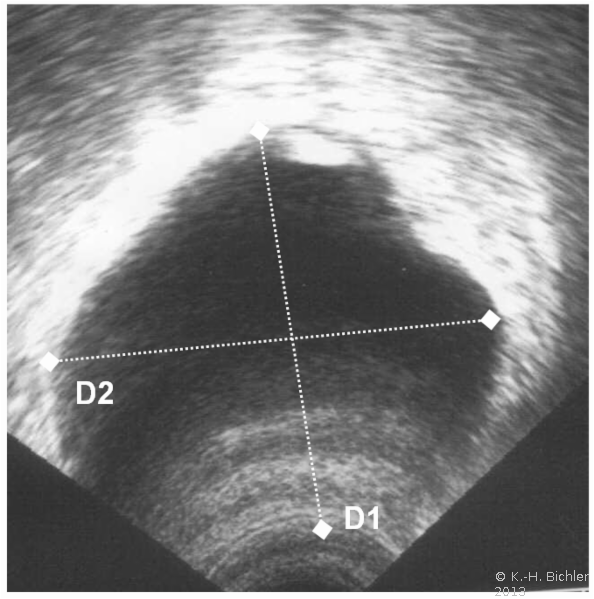

Sonographisch wird das Blasenfüllungsvolumen unmittelbar nach der Miktion in 3 Diagonalen vermessen und nach der Überschlagsformel berechnet:

Restharn [ml] = Länge [mm] x Breite [mm] x Höhe [mm] x 0,55